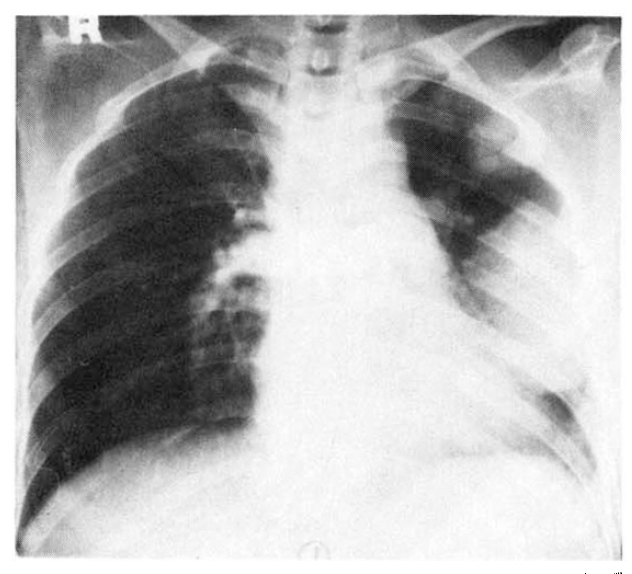

A perfusion lung scan was done as part of a preoperative evaluation for lobectomy of the lung. It showed total nonvisualization of the left lung (Fig. 4).

Fig. 4.

A perfusion lung scan reveals total nonvisualization of the left lung.